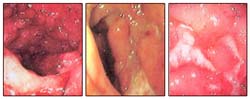

Colitis Ulcerosa en de ziekte van Crohn

De dikke darm wordt ook wel colon genoemd. Algemeen gesproken heeft het colon drie verschillende functies. Hij absorbeert en slaat de stoelgang op en hij verteert voedingsstoffen die niet geabsorbeerd worden. De bacteriële inhoud van de dunne darm is slechts eentiende van de bacteriële inhoud van het colon. Deze bacteriën absorberen de onverteerbare vezels en zetten deze om in bio-chemicaliën zoals acetaat, propionaten en butyraten. Hierbij komt nog dat de bacteriën verschillende gassen en pigmenten produceren die de stoelgang vormen. Deze bio-chemicaliën dienen twee verschillende functies. Zij vormen de pH van het colon en houden deze onder controle en ze voeden de coloncellen. Deze functies voorkomen dat de afgescheiden toxines opnieuw geabsorbeerd worden.

Een ontsteking aan het colon kan verschillende oorzaken hebben. Deze ontsteking aan het colon noemen we Colitis. Een persoon die een ontsteking aan het colon oftewel Colitis heeft, kan last hebben van de volgende symptomen, waardoor de ziekte gemakkelijk te herkennen is:

Colitis Ulcerosa:

Colitis Ulcerosa komt alleen in de dikke darm voor. Hoe erg de dikke darm aangetast is door de ziekte en de symptomen van de ziekte variëren van persoon tot persoon. De meest voorkomende symptomen zijn: I) veelvuldig diarree, II) bloedige diarree, III) slijm in de ontlasting. Als het bloeden niet goed behandeld wordt, kan dit leiden tot anemie, moeheid en zwakte. Bij sommige mensen ziet men ook hoge koorts, buikpijn, rode ogen, verspringende gewrichtsklachten (migrating arthralgia), verlies van eetlust, gewichtsverlies, huidproblemen waarbij pijnlijke paars-rode bultjes ontstaan op de schenen en kuiten (erythema nodosum), humeurigheid en bij kinderen groeistoornissen. Colitis Ulcerosa wordt bepaald naarmate de dikke darm aangetast is. Als alleen het rectum is aangetast met Colitis Ulcerosa, wordt het Ulceratieve Proctitis genoemd. Als rectum en colonsigmoïdeum zijn aangetast, heet het Sigmoproctitis. Als de gehele linkerkant van het colon, het rectum, de colonsigmoïdeum en het colon descendens aangetast zijn, heet dit linkszijdige Colitis. De term pancolitis wordt gebruikt als het hele colon is aangetast door Colitis Ulcerosa. Soms wordt het laatste gedeelte van de dunne darm, ileum genoemd, aangetast door Colitis Ulcerosa. Het aangetaste deel van de dunne darm raakt dan ontstoken. Dit leidt tot de ontwikkeling van zweren en er ontstaan symptomen als bloederige diarree, buikpijn en koorts.